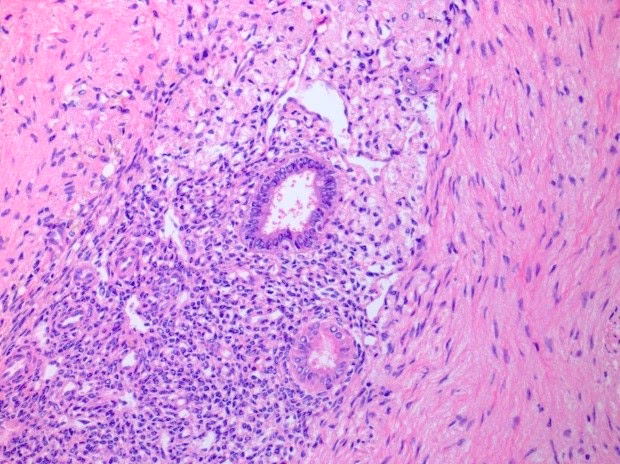

Endometriose er en kronisk, men godartet, sygdom, hvor væv, der ligner livmoderslimhinden (endometriet), vokser uden for livmoderen. Dette ektopiske væv reagerer på hormonelle svingninger i menstruationscyklussen på samme måde som den normale slimhinde, hvilket betyder, at det vokser og bløder hver måned. Men i modsætning til menstruationsblod har dette blod ingen vej ud af kroppen. Dette fører til ophobning af blod, inflammation, arvævsdannelse (adhærencer) og cyster, hvilket kan forårsage betydelige smerter og andre komplikationer. Tilstanden rammer anslået 5-10% af alle kvinder i den fødedygtige alder og er en af de hyppigste årsager til kroniske bækkensmerter og nedsat fertilitet.

Endometriose kan i princippet opstå mange steder i kroppen, men den er langt hyppigst lokaliseret i bækkenområdet. Læsionerne kan variere i størrelse fra mikroskopiske pletter til store, sammenhængende masser. Placeringen af endometriosevævet har stor betydning for, hvilke symptomer den enkelte kvinde oplever.

- Bughinden (Peritoneum): Den tynde hinde, der beklæder bughulen og bækkenorganerne, er ofte dækket af små endometriose-læsioner.